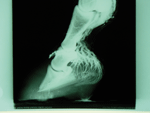

X ray showing seroma and sinking

Dry dorsal seroma

The x-rays will not only show the current position of the coffin bone in relation to the hoof capsule, but can also show any pockets of gas which have filled the void created by the dead laminae.

When fitting a loaded heartbar, any serum or gas pockets should be opened to release the hydrostatic pressure within the hoof and this offers the horse some relief.